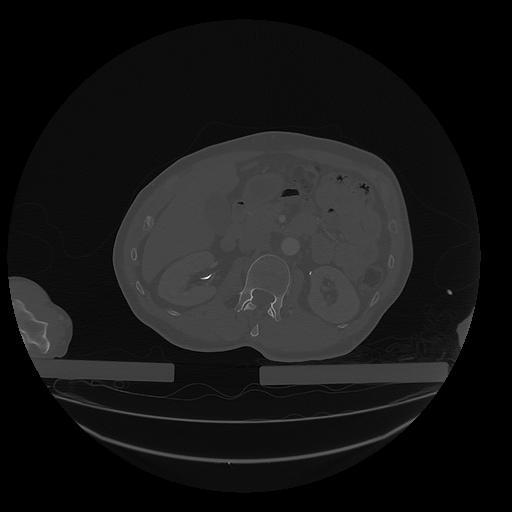

31 PULMON,CE,Vol,1.0,PULMON,,